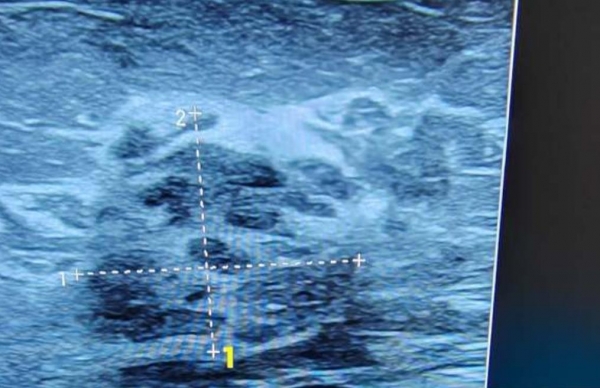

乳腺增生、结节等乳腺问题近年来高发。长期穿戴过紧或不合适的内衣,会让部分区域持续受压,导致乳腺血流不畅,风险略增。而在睡眠或长期静止时不穿内衣,可以减少乳腺结节、局部炎症。官方统计显示,适度裸睡,能使乳腺结节发病率降低12%,有效预防增生。此外,皮肤受损和毛孔堵塞的概率也会相对减少。